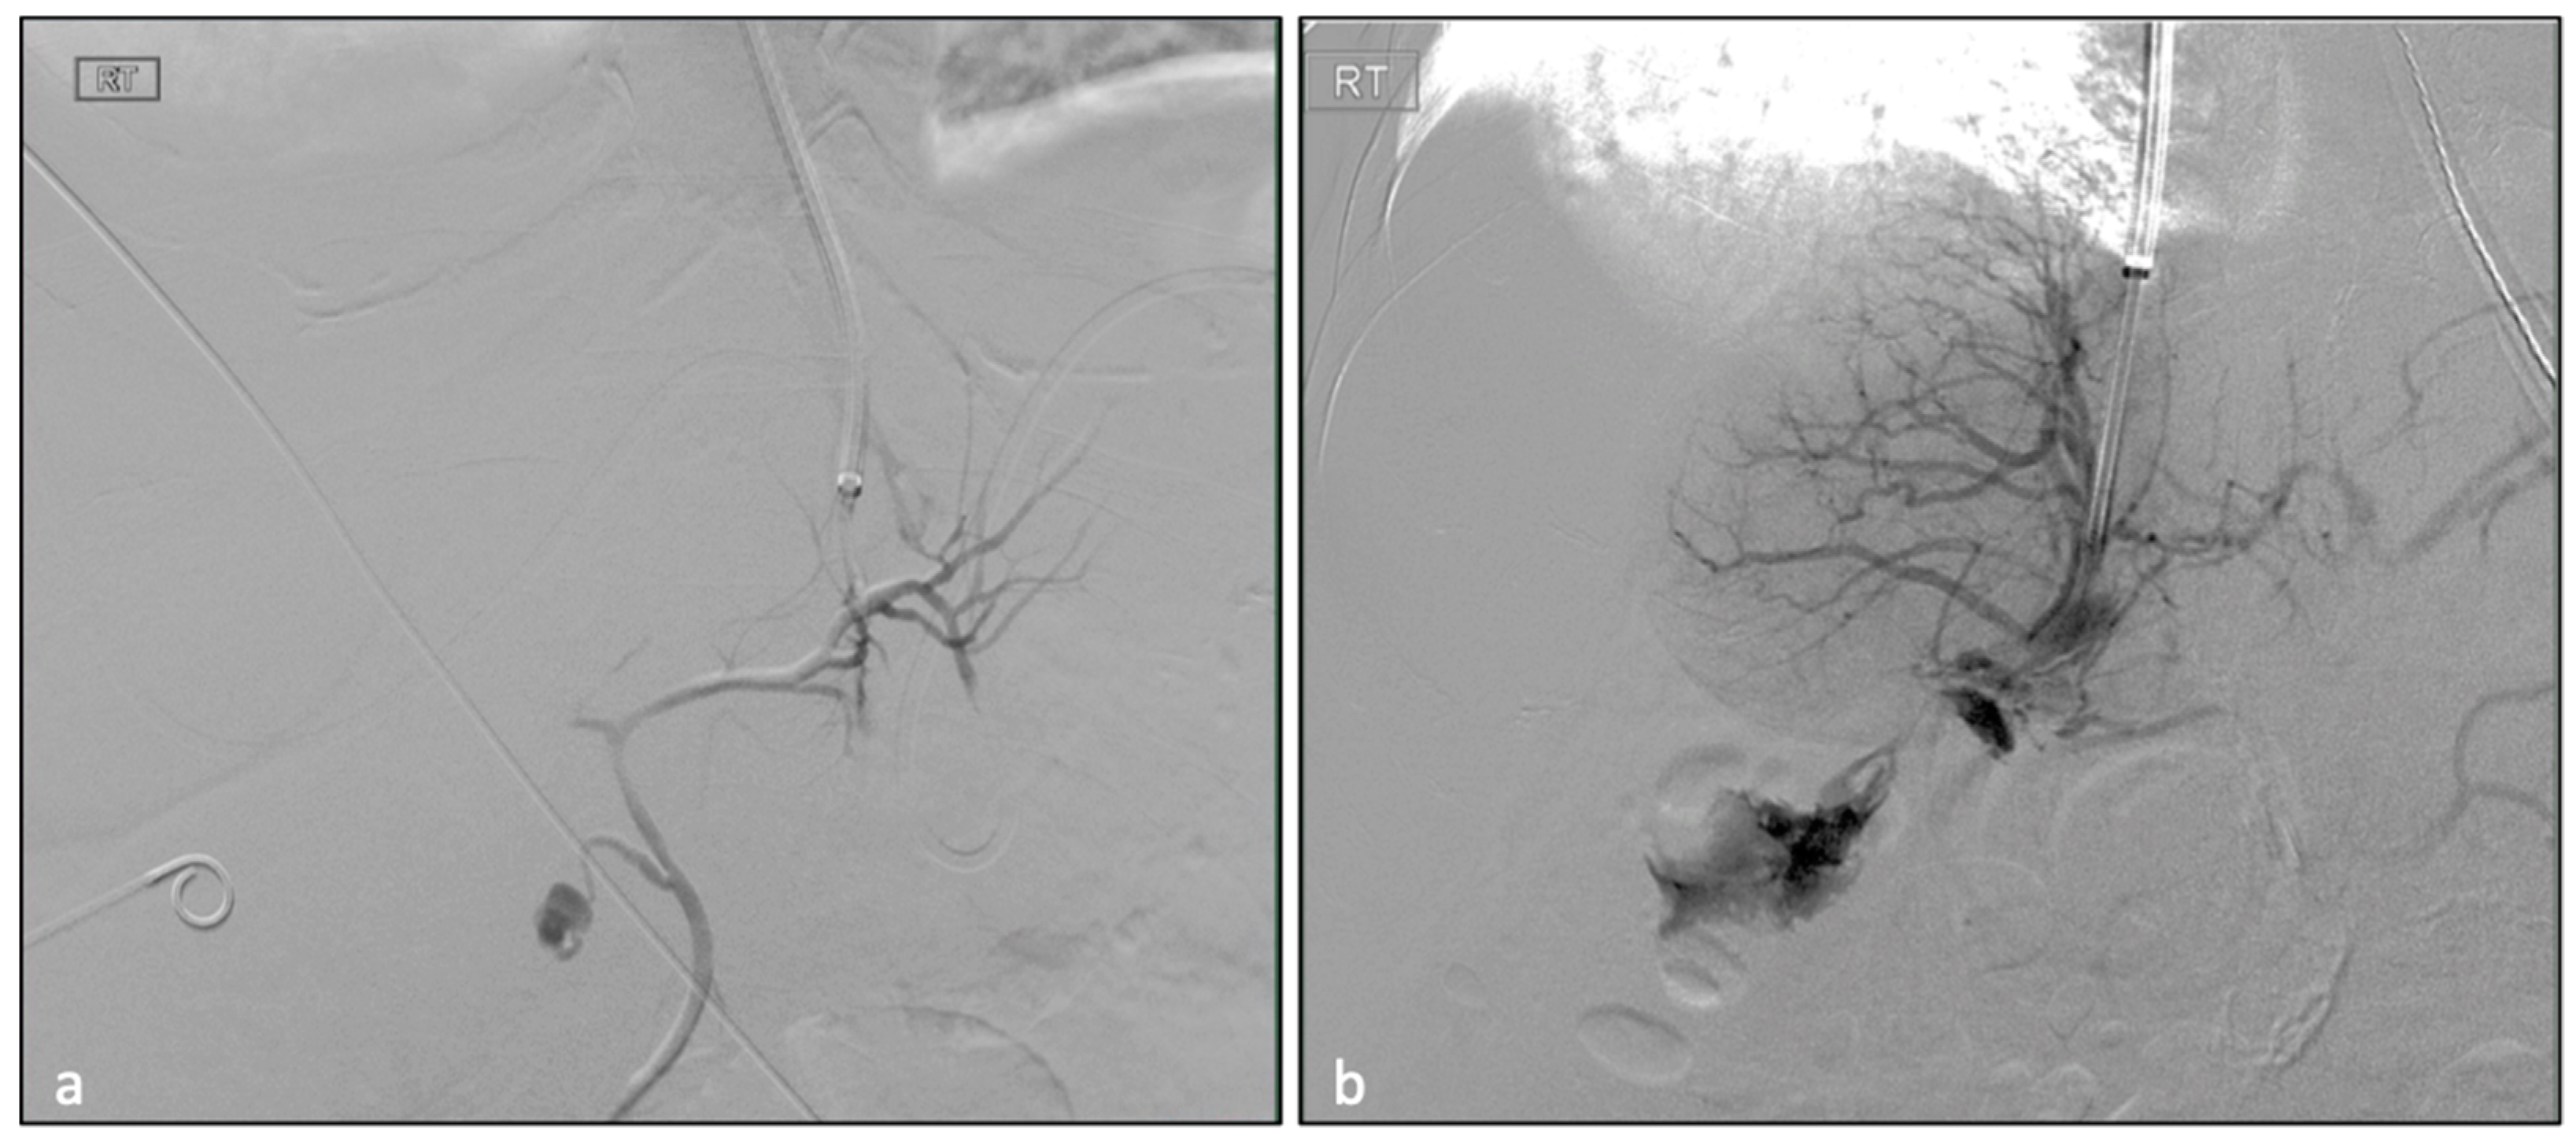

| ID | Biliary Puncture | Hepatic Artery Puncture | Lymphatic Puncture | Capsular Puncture | Clavien-Dindo Grading Complication in 30 Days | Complications | LOS (Days) |

|---|---|---|---|---|---|---|---|

| 6 | X | 0 | 0 | 0 | 1 | Focal segment 7 biliary ductal dilatation | 6 |

| 8 | X | 0 | 0 | X | 4B | Multiorgan failure | 56 |

| 30 | 0 | X | 0 | 0 | 2 | Hemoperitoneum need, blood transfuse | 13 |

| 35 | 0 | X | 0 | X | 2 | Hemoperitoneum need, blood transfuse | 2 |

| 41 | 0 | 0 | X | 0 | 1 | Mild hypotension | 2 |

| 43 | 0 | 0 | X | X | 5 | Hemoperitoneum, hypovolemic shock | 8 |

| 51 | X | X | X | X | 5 | Arteriobiliary fistula | 26 |

| 54 | 0 | 0 | 0 | X | 1 | Mild hypotension | 4 |